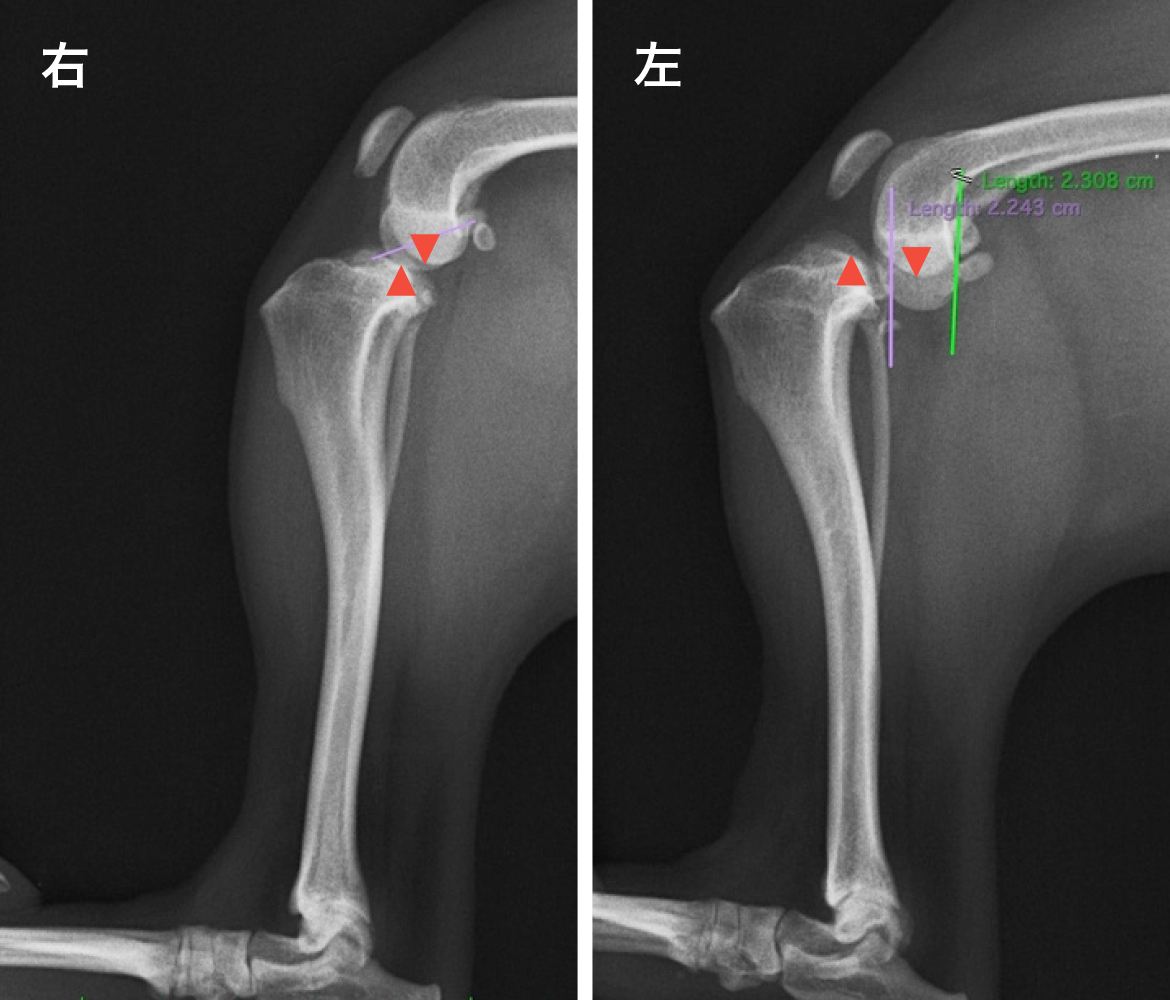

• Before

前十字靭帯断裂 (左後肢)

脛骨が右後肢と比較して前方に変位しているのがわかります。脛骨と大腿骨が接する面がズレて開きができ、上からも下からも力の受け渡しができない状態です。